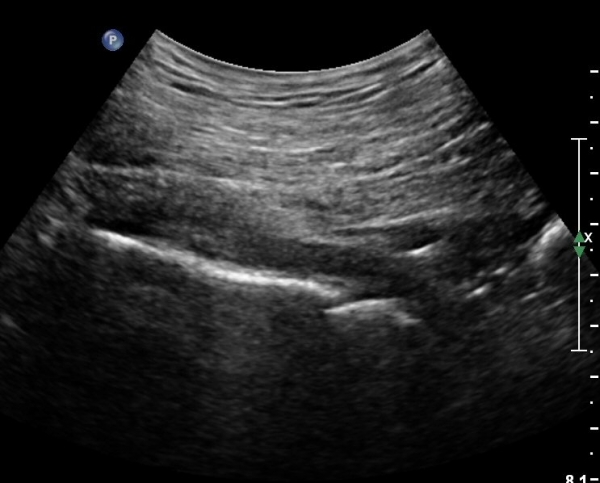

ÈÄ»óÀå°ñ±Ø ¿ÜÃø¿¡ ŽÃÊÀÚ¸¦ ¼öÆòÀ¸·Î ´ë¸é ½ÉÃþÀ¸·Î Àå°ñÀÌ °üÂûµÇ°í Àå°ñ Ç¥Ãþ¿¡ ´ëµÐ±Ù°ú ÁߵбÙÀÌ °üÂûµÈ´Ù(»çÁø 1).